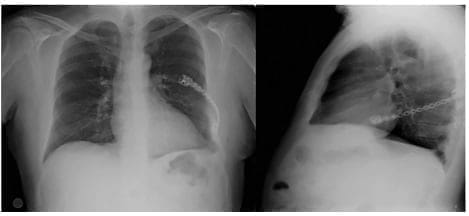

Estos cambios correspondieron a un desorden xantogranulomatoso infiltrativo compatible con la enfermedad de Erdheim Chester. Las pruebas de inmunohistoquímica CD68 positiva, CD163, CD1A y CK negativas, confirmaron el diagnóstico. Después de 2 años de seguimiento el paciente está asintomático y los controles radiológicos son normales (Figura 3).

Figura 3. Radiografía de tórax normal al segundo año de control posoperatorio.